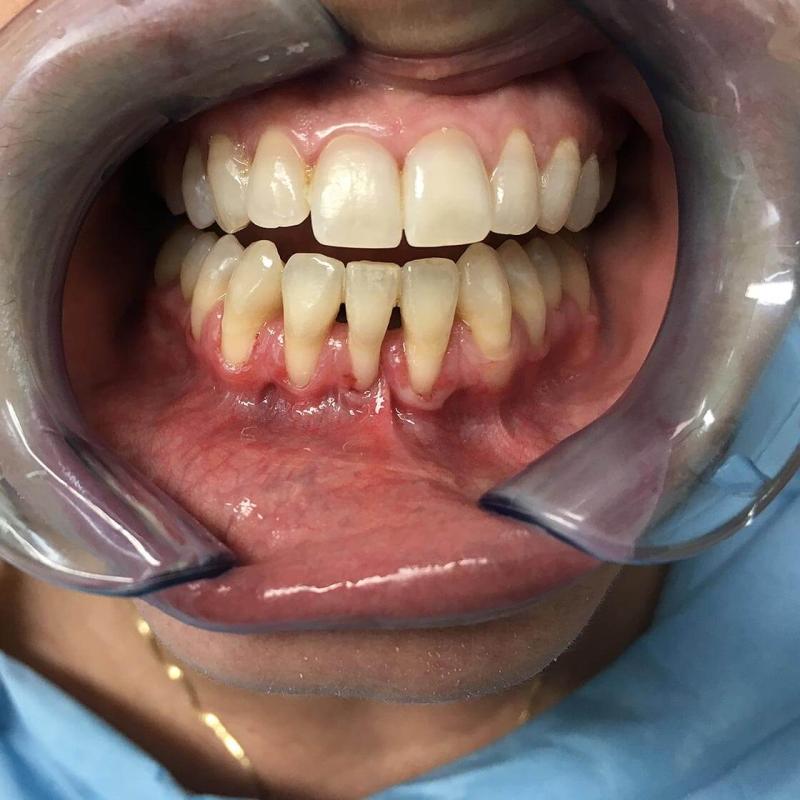

La parodontologia controlla il benessere delle strutture portanti dei denti (gengive e osso di sostegno) cercando di prevenire o curare la piorrea che nella popolazione adulta è la più frequente causa di perdita dei denti.

Oggi più che mai viene richiesta la copertura di esposizioni radicolari mediante la chirurgia estetica mucogengivale. Inoltre con la cura della piorrea si mantiene in buono stato la salute generale del paziente prevenendo complicanze cardiovascolari e diabetiche.